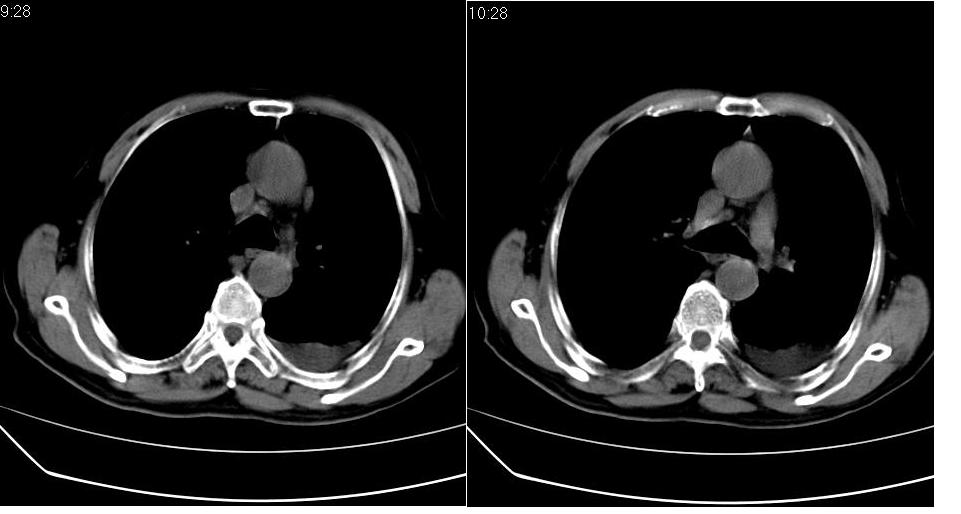

左下肺体积缩小,密度增高,见片增密影。边界模糊,见支气管充气像,肺门纵隔无异示,心脏气管左移,左侧胸腔少量积液。考虑肺部感染伴部分肺不张[有脑梗塞病史坠积性肺炎可能]

1、左肺下叶后基底段炎症并膨胀不全。

2、左侧胸腔积液。

左下肺体积缩小,密度增高,并见大片状致密影,边界模糊,其内见支气管充气像,肺门纵隔无异常,心脏气管左移,左侧胸腔少量积液。考虑:左肺炎性病变伴不张。

左肺下叶感染,肺膨胀不全,左胸腔积液,不能排除结核性病变

3.两肺慢支改变。